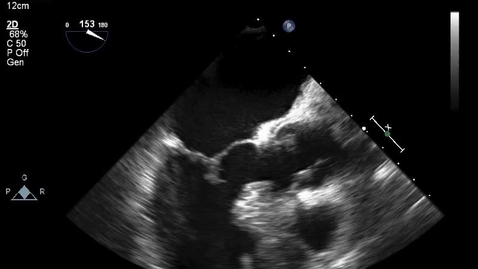

Hypertrophic cardiomyopathy

HCM Clip 4. Post myectomy

HCM Clip 3. Pre myectomy